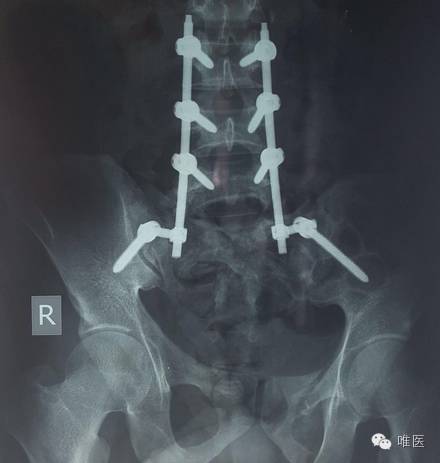

术中直接复位有些困难,部分咬除骶一和骶二的椎板,探查见硬脊膜是完整的,通过髂腰螺钉的提拉和杠杆作用一点一点复位。

▼ 术后照片